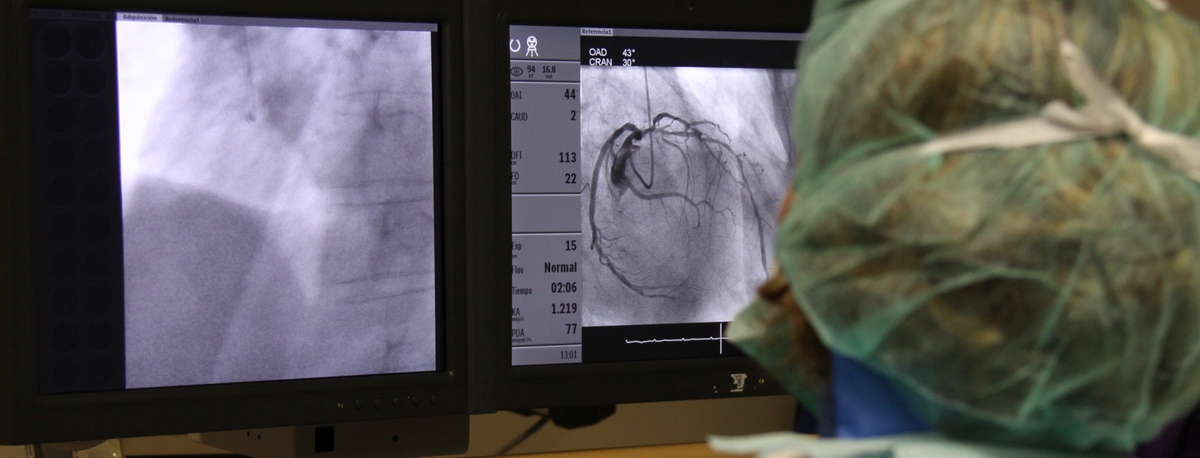

Instituto del Corazón Quirónsalud Teknon

Experience treating cardiovascular diseases

The institute is staffed with specialists in angiology, vascular surgery, and endovascular surgery, who handle everything from diagnosing to monitoring circulatory system illnesses.Cerebral embolism and pulmonary thromboembolism are some of the leading causes of death due to vascular problems.

Our team specialises in minimally invasive techniques, using endovascular techniques without surgery, which allow vascular prostheses to be implanted to resolve dilations or aneurysms of the arteries. We also offer all treatments for venous and peripheral arterial disease, including carotid artery disease.